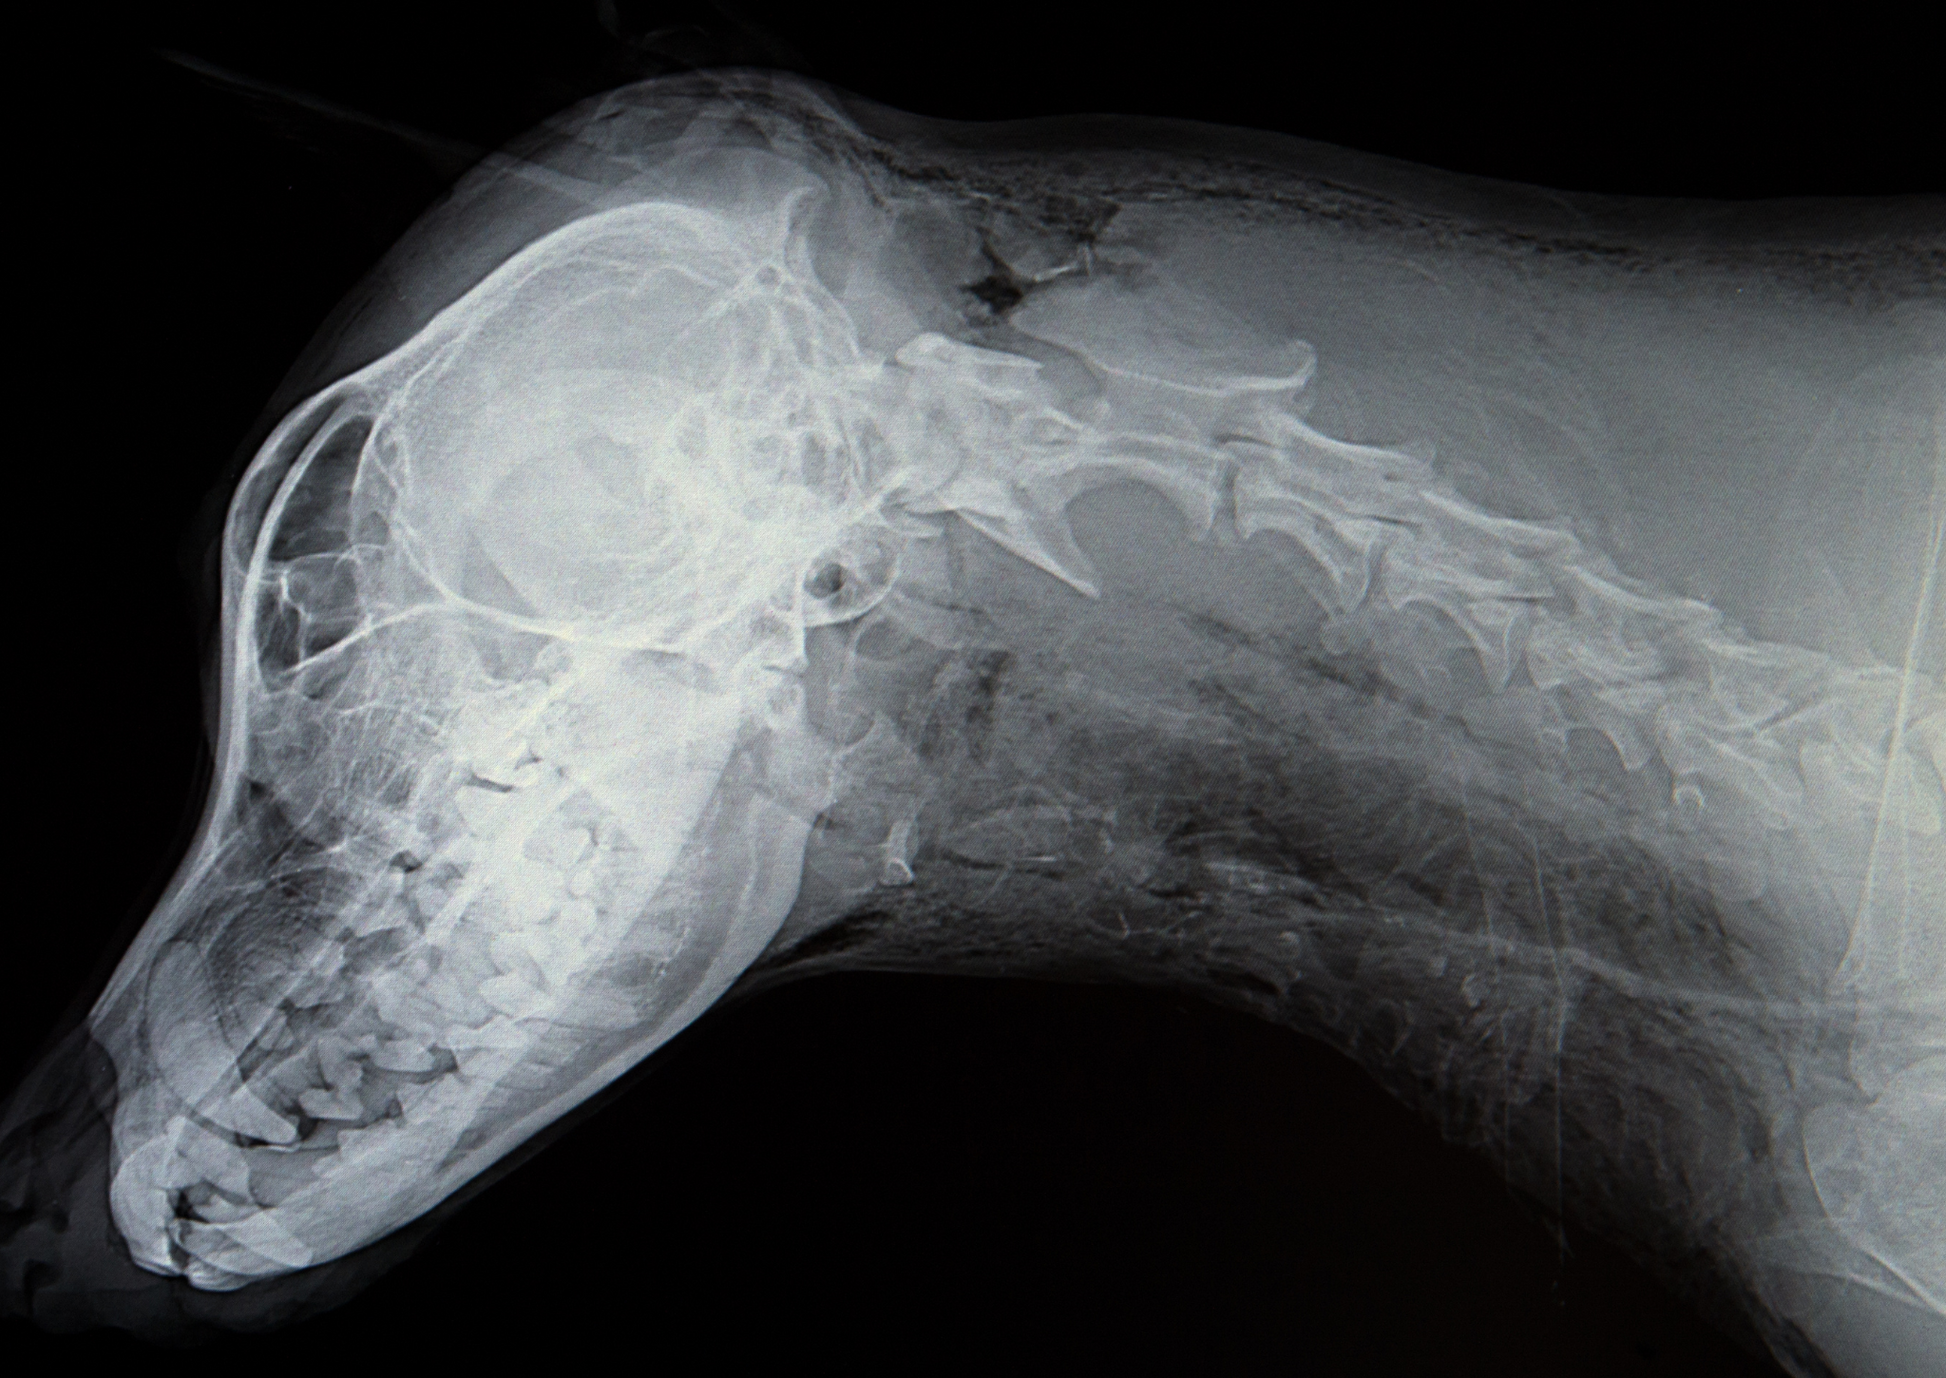

What's next for veterinary imaging - insights from human medicine